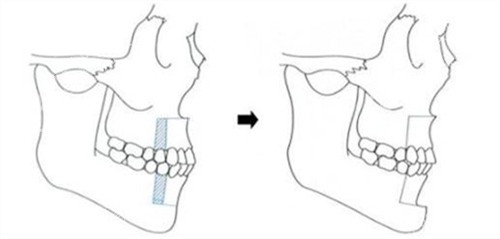

何医生团队用三维CT和咬合模型分析我的骨骼问题,明确告诉我:“单纯正畸改善有限,双鄂截骨才能让上下颌骨回归正确位置。”

第6个月:复诊拍片显示骨骼愈合良好。何医生指着侧脸对比图说:“现在这弧度才符合美学标准。”